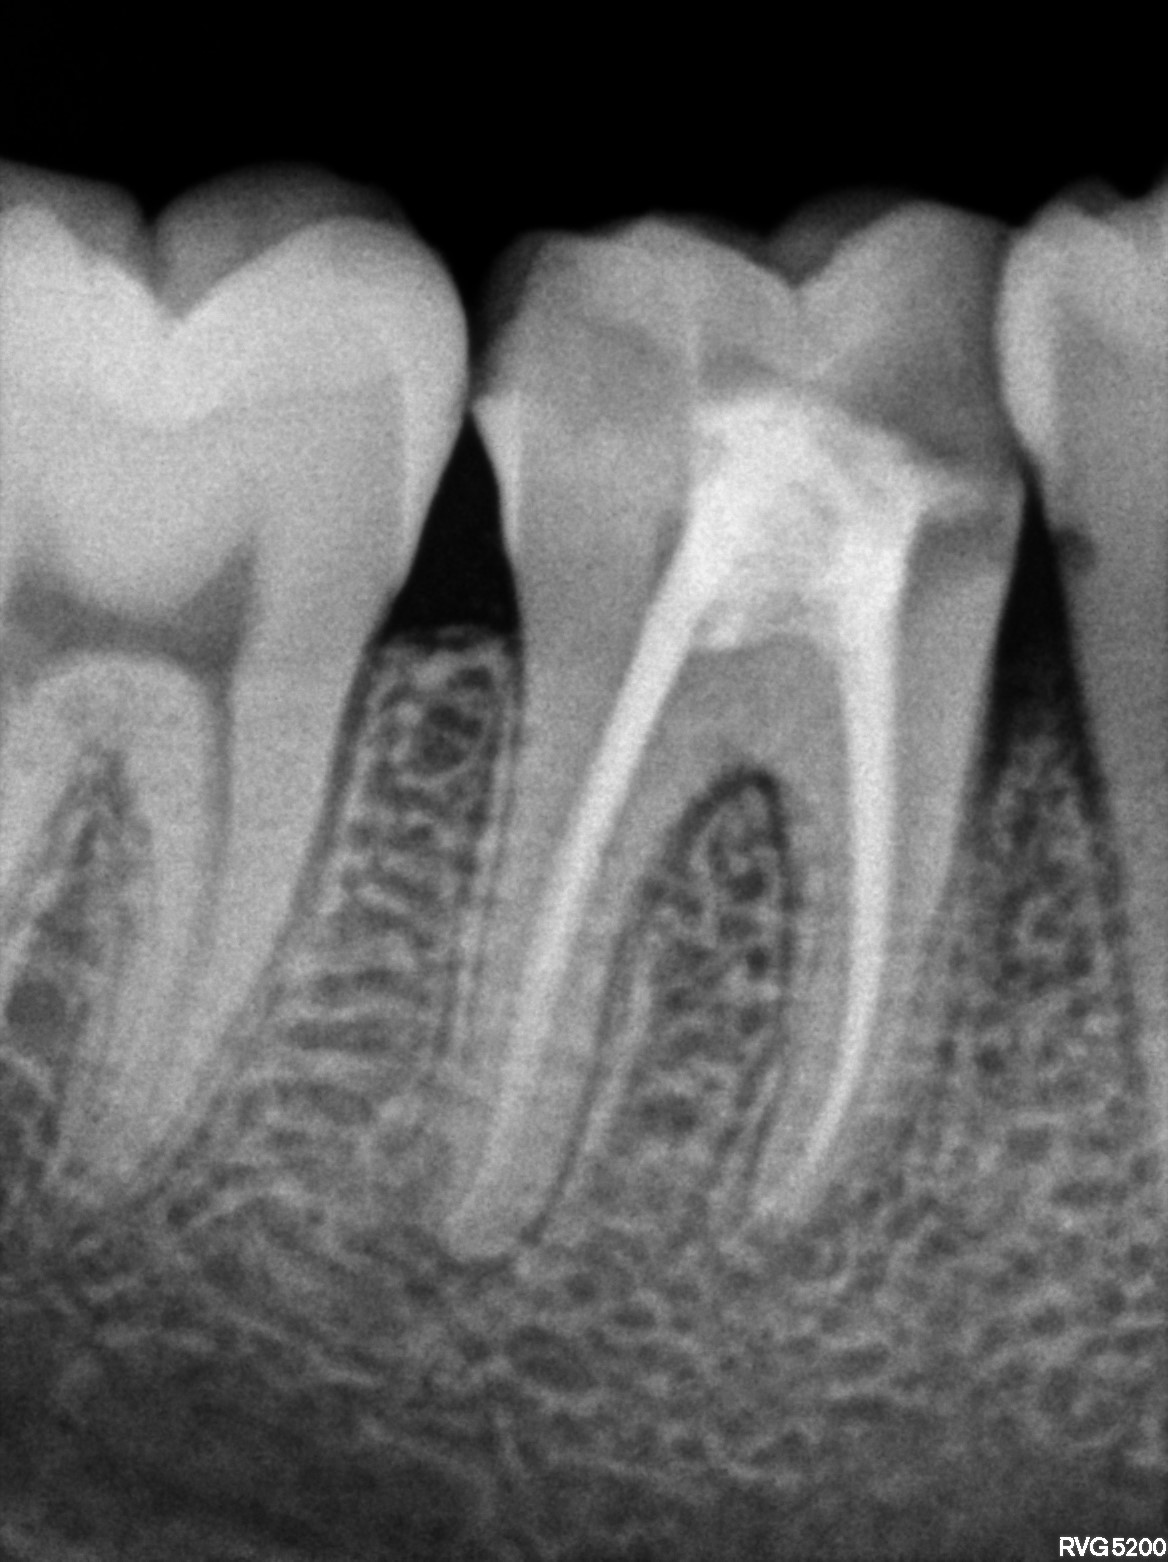

Dental Radiographs FHIR: DocumentReference · LOINC 24641-7

36.jpg

24641-7

46.jpg